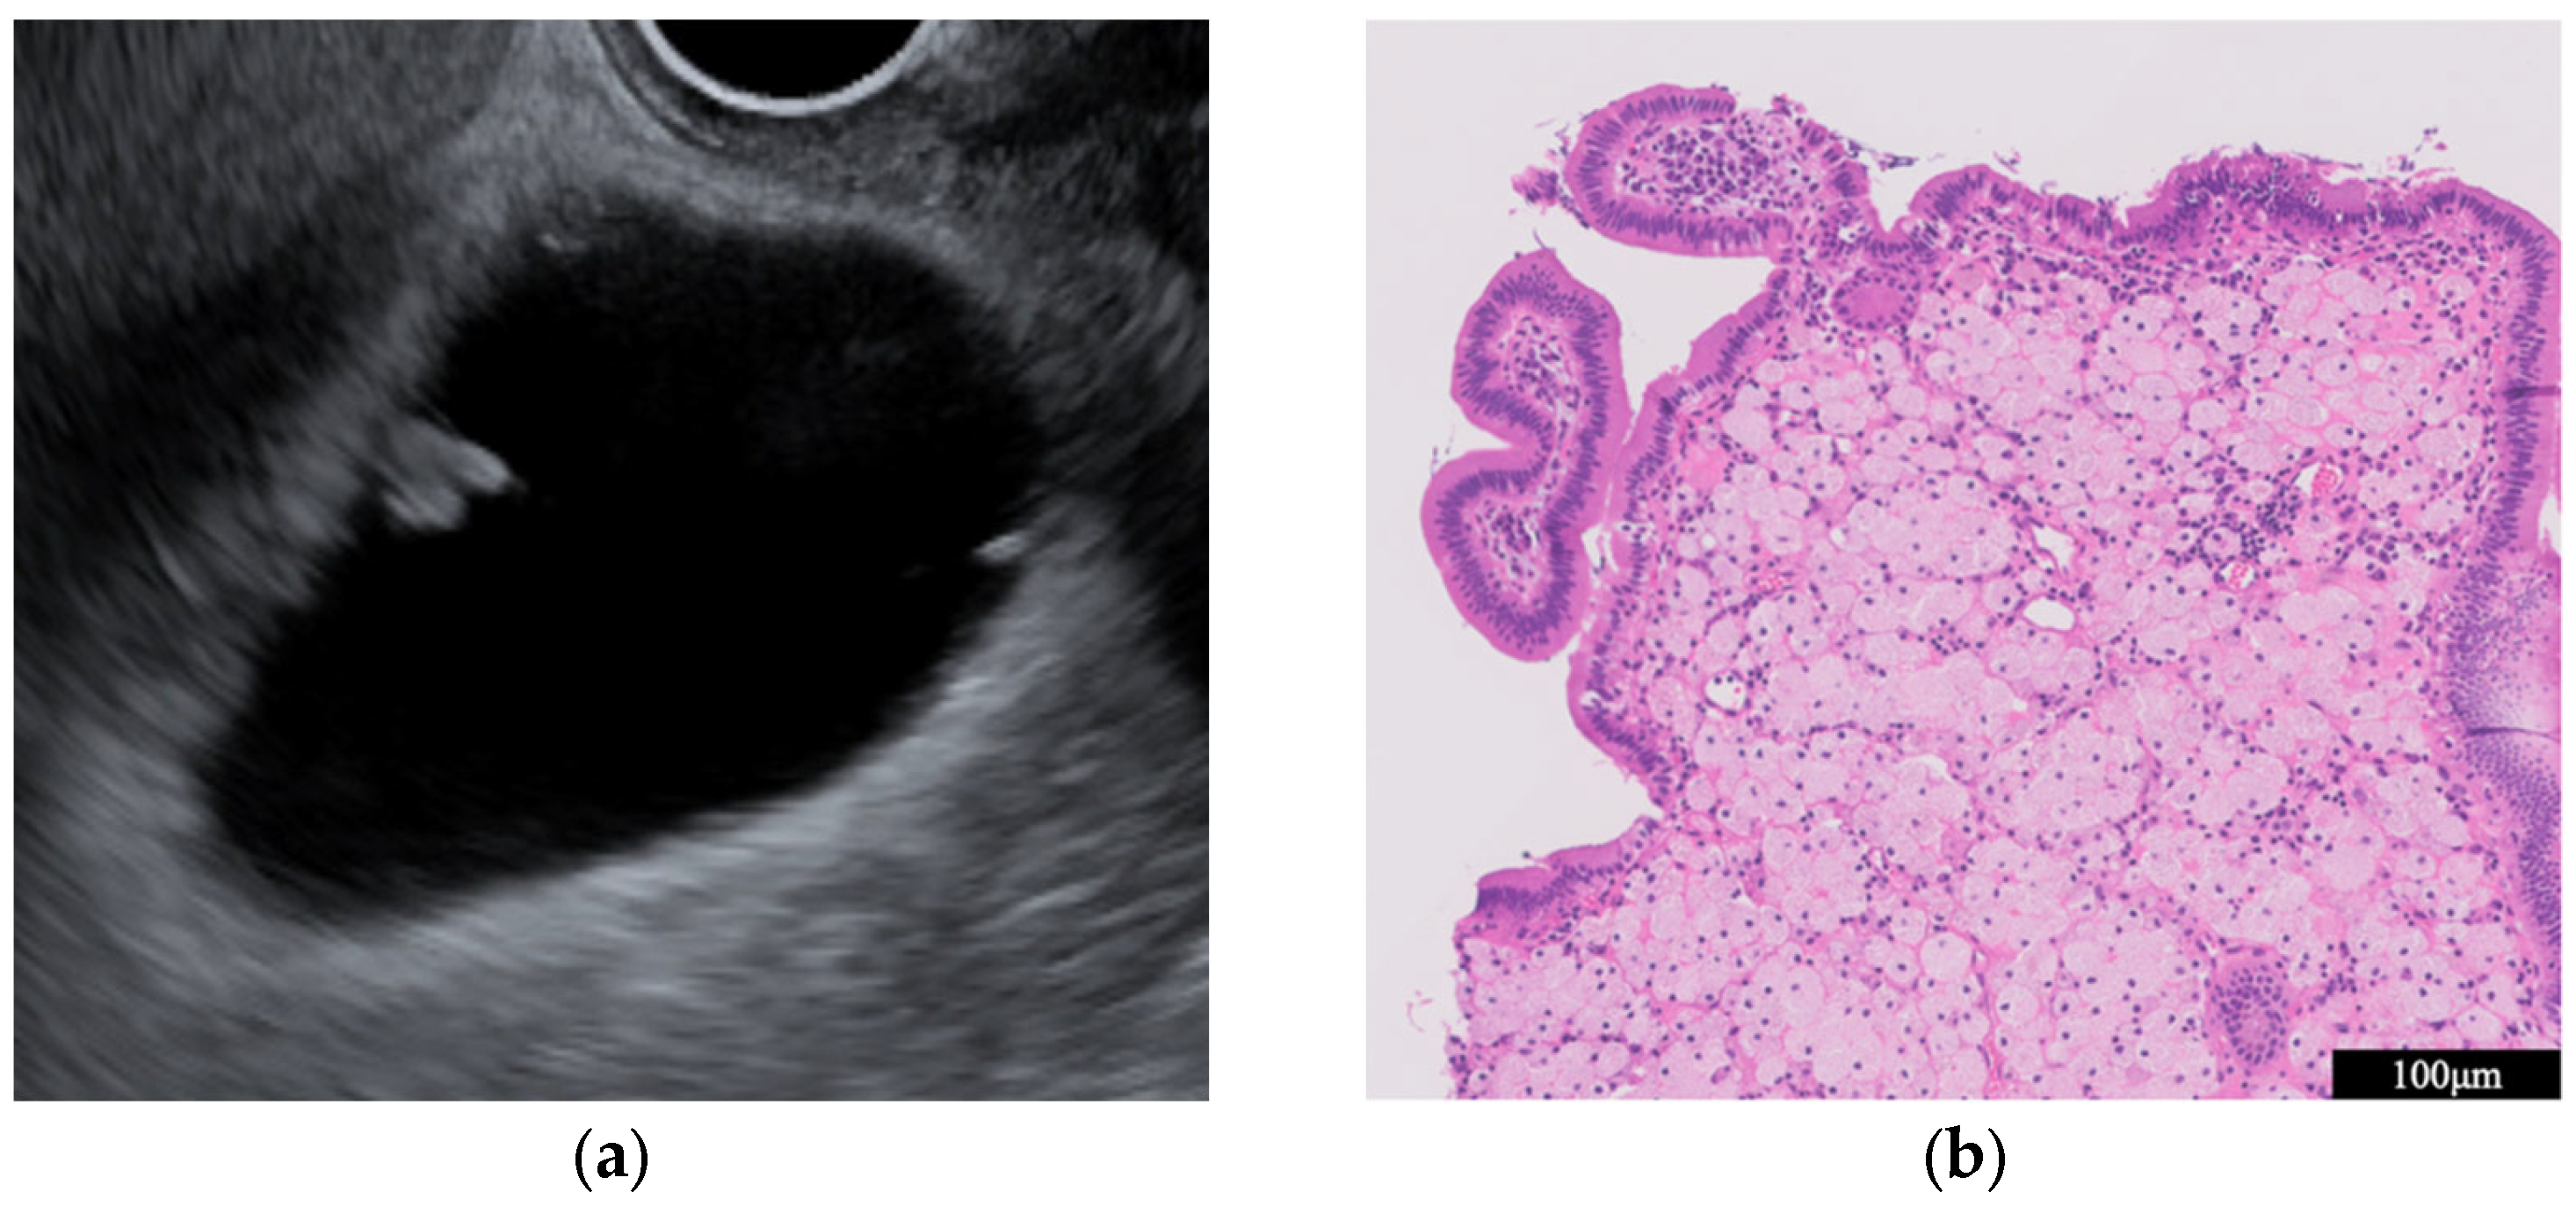

- Adenomyomatosis

- Immunoglobulin G4-related sclerosing cholecystitis (IgG4-CC) (Figure 3)